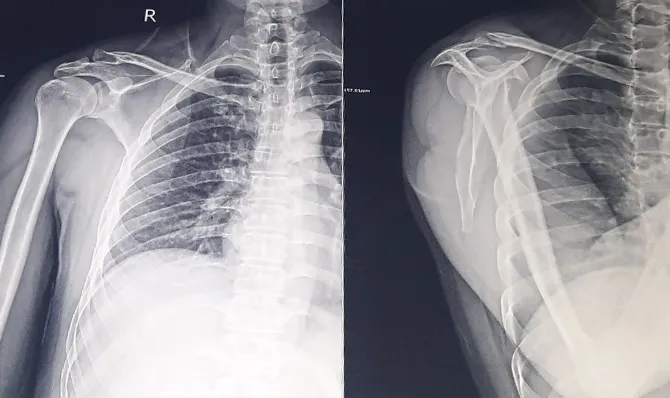

Anh Bùi Văn D (SN 1983) bị ngã, gãy xương đòn cánh tay sau khi hút thuốc lào buổi sáng. Ảnh: ĐT |

Sau khi chụp X-Quang, bác sĩ kết luận anh D bị gãy xương đòn vai. Ảnh: ĐT |